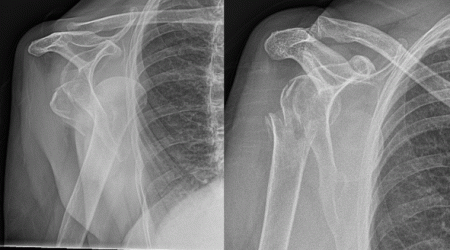

Fracture-dislocation in a 78 year old lady